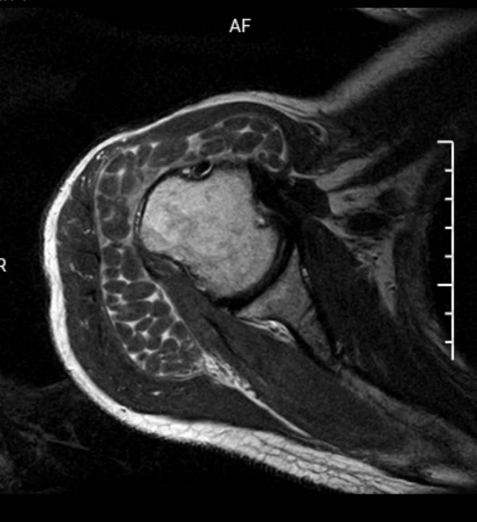

X 线检查无特殊意义,以 MRI 检查最为敏感,关节周围软组织可见不同程度水肿,肩峰下可见积液,以及大量直径不等(1 ~ 10 mm)的类圆形占位,与周围肌肉组织相比呈等 T1 稍长 T2 信号。

无明显症状的关节病,米粒体滑囊炎会被忽略漏诊。主要需与色素沉着绒毛结节性滑膜炎 (PVNS) 和滑膜软骨瘤相鉴别。鉴别诊断要点主要以 MRI 为主。

化生软骨往往呈叶状,未钙化时的 T1 像为等信号,T2 加权像为高信号;已经钙化的则 T1 和 T2 加权像均为高信号。